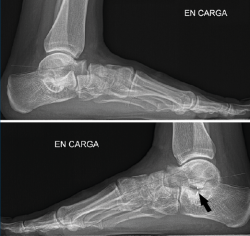

Figura 10. Tras la cirugía: primer caso a la izquierda, segundo caso a la derecha. Las flechas señalan el pie intervenido.

A los 6 meses (Figura 10), la evolución es correcta, con corrección clínica y radiológica del plano/valgo y manteniendo cierta movilidad de la articulación subtalar (15°).

En el primer caso (Figura 11), presenta el siguiente balance articular: flexión = 45°; extensión = 15°; inversión = 10°; eversión = 5°. Valgo talar de 10°. Refiere molestias discretas en el seno del tarso a la hiperextensión. Marcha correcta. Escala AOFAS del tobillo: 82 (30-42-10) . Los ángulos radiológicos finales son: Moreau-Costa-Bartani interno = 134°; declinación talar = 18,3°; Meary = 1,6°; Kite = 16,2°; taloescafoideo= 63,3°.

Figura 11. Radiografía del segundo caso poscirugía: corrección del pie plano y visualización de la endortesis (flecha) en el seno del tarso.

En el segundo caso (Figura 12), presenta un balance articular: flexión = 45°; extensión = 20°; inversión = 10°; eversión = 5°. Valgo del talón de 9°. La paciente refiere alguna molestia sin definir en el retropié y realiza una marcha correcta. Escala AOFAS del tobillo: 84 (30-44-10). Los ángulos radiológicos finales son: Moreau-Costa-Bartani interno = 131°; declinación talar = 13,8°; Meary = 1,1°; Kite = 15,1°; taloescafoideo = 77,4°.

Figura 12. Radiografía de perfil de ambos pies del segundo caso. Flecha en la endortesis del pie intervenido.